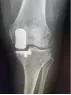

微创单髁置换手术就是微创保膝理念的有效解决办法之一。它也叫做部分膝关节置换术,手术只是将膝关节内侧部分磨坏的股骨和胫骨骨头切除,装上非常耐磨的人工材料,保留外侧未磨损的关节和关节内所有韧带。而且手术可以通过比全膝置换小得多的伤口来完成,其创伤小、出血少、恢复快、假体寿命长、功能恢复程度高等一系列优点正逐步的显示在世人眼前。

宣武医院骨科关节组在曹光磊主任的带领下,正在以微创保膝为理念,阶梯化治疗膝关节骨关节炎。目前宣武医院骨科关节组是北京最早开展保膝化治疗的团队之一,通过细致的体格检查、规范的影像学检查和术中证实,严格把握患者的手术适应症,将众多“前内侧骨关节炎”的患者寻找出来,选择微创单髁置换术,取得了很好的效果。